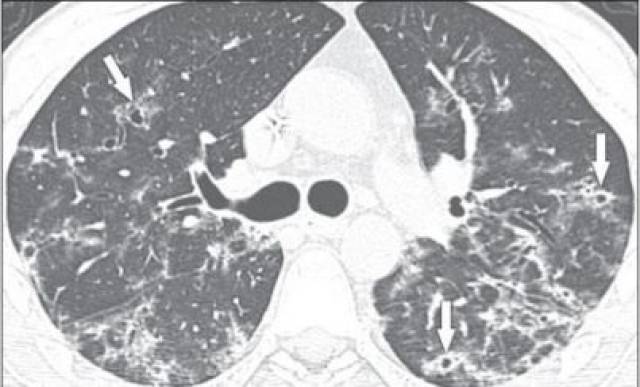

参考文献:kanne j p, yandow d r, meyer c a.